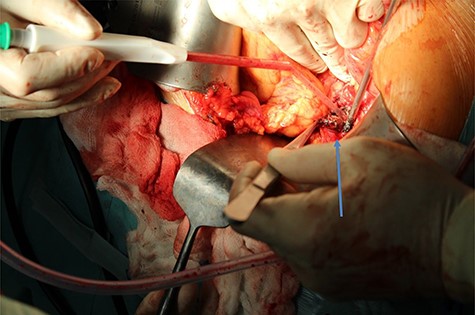

We present the case of 46-year-old female patient suffering from spontaneous hypoglycemia. She was admitted to our hospital due to worsening clinical symptoms. At first, she underwent a 72-hour monitored fast and biochemical testing for endogenous hyperinsulinism, which proved positive. Once the other causes of spontaneous hypoglycemia were excluded, we started the process of localization of insulinoma. Then the patient underwent endoscopic ultrasonography (EUS) of pancreas with the find of hypoechogenic, well demarcated, hypervascular tumor in the head of pancreas size of 12.4 × 10.5 mm (Fig.1). Computed tomography (CT) examination of abdomen followed up and tumor of pancreatic head, corresponding with the diagnosis of insulinoma, was found (Fig. 2). It was located nearby pancreatic and biliary duct. Because of serious clinical symptoms, an early surgical treatment was indicated. Based on the evaluation of the surgeon to perform the less radical surgery, it was suggested to enucleate the tumor with preoperative stenting of pancreatic and biliary duct. Two days before the surgery, ERCP with insertion of pancreatic and duodenobiliary stent was performed (Fig. 3). With regard to the patient's preference and overweight, laparotomic approach was selected. Determination of the exact position of tumor was difficult, insulinoma was hardly palpable. We used intraoperative ultrasonography to identify the exact location of tumor (Fig. 4). Then the surgeon palpated the inserted stents and the insulinoma was identified intrapancreatically, 3–4 mm nearby pancreatic and bile duct. Enucleation of tumor was performed by harmonic scalpel (Fig. 5). During the surgery, the right position of stents was verified by touch. After enucleation, there was no presence of bleeding, the defect was filled with tissue glue (Fig. 6). Macroscopically, tumor was round shaped, well capsulated, size 1 cm (Fig. 7). During postsurgery period, the patient was stable and with no signs of complication. On the sixth postoperative day, endoscopic removal of pancreatic stent was carried out. Patient was discharged from the hospital on the eight postoperative day. Duodenobiliary stent was left in ductus choledochus for 1 month.

Enucleation of insulinoma by using of harmonic skalpel (arrow shows enucleated insulinoma).